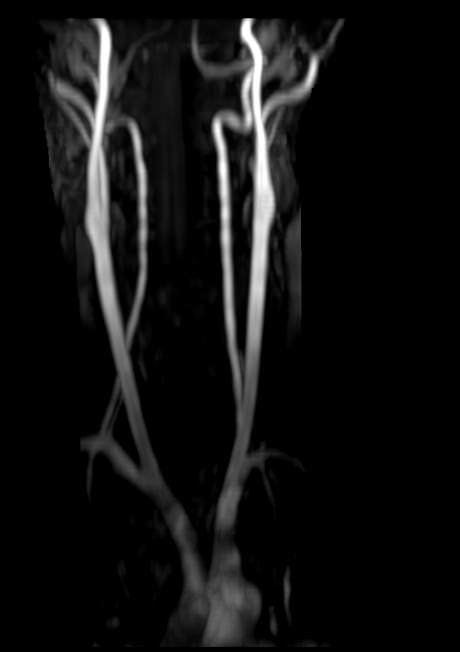

Патологические изменения в сосудах шеи могут вызвать транзиторные ишемические атаки (преходящие нарушения мозгового кровообращения) и инсульты, которые являются частой причиной инвалидизации и смертельных исходов.

Наиболее частая причина патологии сосудов – атеросклероз, при котором в стенке артерии образуются холестериновые отложения в виде утолщения и впоследствии формируются бляшки. Атеросклеротические бляшки с течением времени сужают просвет сосудов, вплоть до полной окклюзии. Кроме того бляшки имеют склонность к изъязвлению и образованию тромбов. Реже встречаются воспалительные изменения сосудов (васкулиты). В некоторых случаях сдавление магистральных артерий шеи может происходить за счет патологии позвоночника, опухолевого процесса или травм.

Для того, чтобы оценить состояние шейных позвонков с прилегающими тканями и одновременно визуализировать крупные сосуды шеи, в нашей клинике выполняется комплексное обследование, включающее два протокола: МРТ шейного отдела позвоночника и МР-ангиографию шеи.

В клинике «Доступная медицина» комплексное обследование шейного отдела позвоночника одновременно с МР-ангиографией шеи проводится на новейшем высокопольном томографе экспертного уровня TOSHIBA VANTAGE TITAN 1,5 Тесла, который производит послойное сканирование исследуемой зоны в разных плоскостях, затем при помощи компьютерных программ преобразует полученные данные в трехмерные изображения шейного отдела позвоночника и кровеносной системы, что позволяет проводить точную диагностику и назначать пациенту своевременное лечение.

• участки сужения, извитость, образование петель и перегибов сосудов;

• ангиомы, сосудистые мальформации.